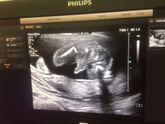

Были мы сегодня на втором скрининге, по месячным 21 неделя ровно, по УЗИ 20, пдр - 6 октября, все у нас в норме, весим 330 гр, и нам подтвердили мальчика ✌️?

Со всех сторон мой малыш показался)